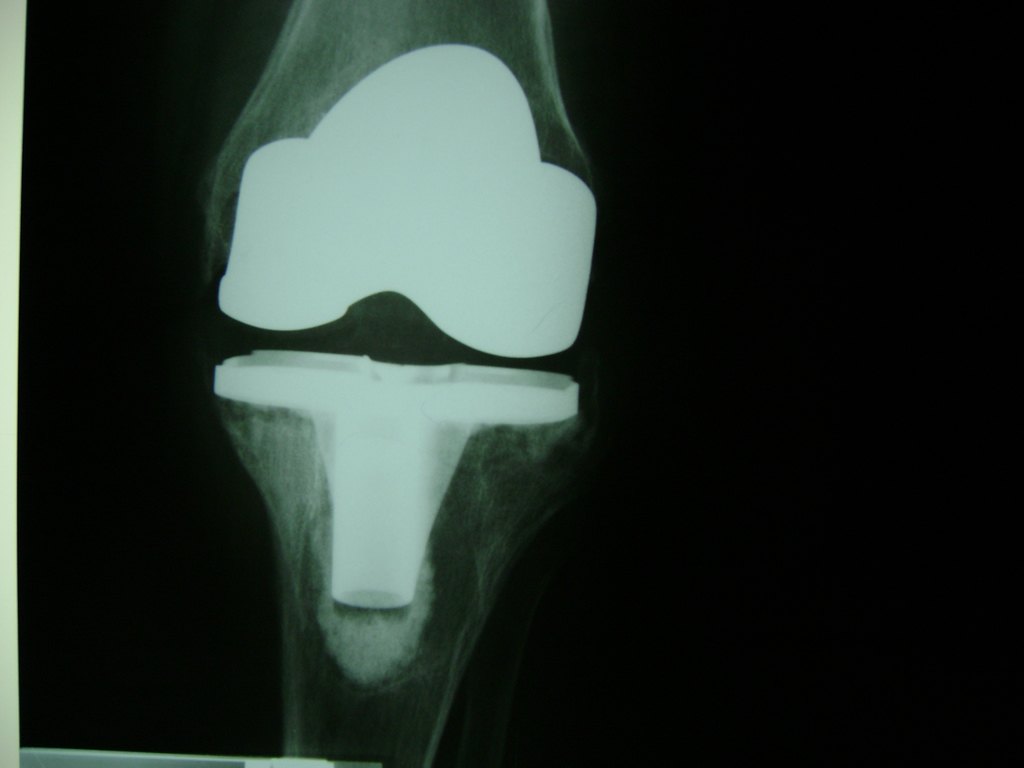

Cirugía de Fémur - Rodilla

La artroscopia de rodilla es un cirugía en el cual la estructura interna de la articulación es examinada ya sea para realizar un diagnostico o para realizar un tratamiento, este procedimiento se realiza utilizando un instrumento parecido a un pequeño tubo llamado artroscopio.